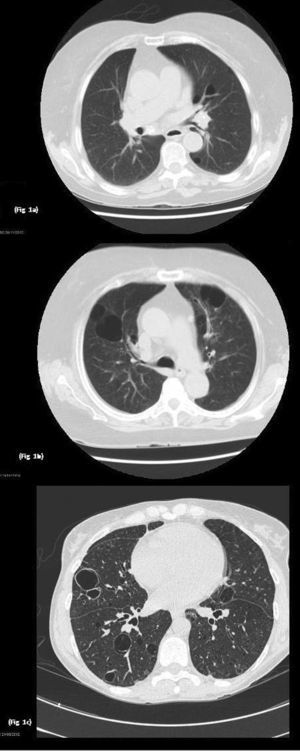

Imágenes TACAR: a) Se observa enfisema centrolobulillar e imágenes quísticas; b) Lesiones pulmonares quísticas bilaterales, algunas de ellas con septos en su interior, bronquiectasias por tracción en ambos lóbulos inferiores, áreas de enfisema pulmonar centrolobulillar y paraseptal y tractos fibróticos, y c) Se evidencian múltiples imágenes quísticas pulmonares de pared fina bilaterales.

Paciente 1Mujer de 74 años diagnosticada de SSp de 18 años de evolución. Presentó manifestaciones extraglandulares tales como, vasculitis tipo PAN. En las pruebas de laboratorio desatacó hipergammaglobulinemia, anticuerpos anti-Ro y anti-La positivos. En tratamiento con azatioprina 50mg/día vía oral. Durante el seguimiento presentó disnea grado funcional II. Se realizaron pruebas funcionales respiratorias que fueron normales, la tomografía axial de tórax de alta resolución (TACAR) evidenció enfisema pulmonar centrolobulillar de predominio en lóbulos superiores e imágenes quísticas de paredes finas de predominio en campos inferiores (fig. 1a). Se mantuvo el mismo tratamiento sin presentar variaciones de dichas lesiones pulmonares en los sucesivos controles.

Mujer de 46 años con diagnóstico de SSp de 20 años de evolución y mieloma IgA kappa. Como manifestaciones extraglandulares había presentado anemia, vasculitis leucocitoclástica, así como poliartritis y parotidomegalia. En tratamiento con hidroxicloroquina (HCQ) 200mg/día, pilocarpina 15mg/día vía oral y rituximab cada 6 meses. En las pruebas de laboratorio destacó aumento de reactantes de fase aguda, anemia y linfopenia, así como hipergammaglobulinemia con elevación de IgG y componente monoclonal IgA kappa. El factor reumatoide (FR), así como los anticuerpos anti-Ro y anti-La, fueron positivos. Durante el seguimiento presentó disnea de grandes esfuerzos. Se realizaron pruebas funcionales respiratorias, evidenciándose alteración de la ventilación restrictiva leve con ligera disminución de la DLCO, el TACAR de tórax puso de manifiesto lesiones pulmonares quísticas bilaterales, algunas de ellas con septos en su interior, de predominio en bases, bronquiectasias por tracción en ambos lóbulos inferiores, áreas de enfisema pulmonar centrolobulillar y paraseptal en lóbulos superiores junto a opacidades lineales y tractos fibróticos en ambas bases pulmonares (fig. 1b). Se mantuvo el mismo tratamiento, sin evidenciarse cambios de dichas lesiones quísticas en sucesivos controles.

Paciente 3Mujer de 78 años con diagnóstico de SSp primario de 15 años de evolución, y amiloidosis cutánea. Las manifestaciones eran predominantemente glandulares (xerostomía y xeroftalmía), sin presentar manifestaciones extraglandulares, en tratamiento con HCQ 200mg/día vía oral. En las pruebas de laboratorio destacó reactantes de fase aguda elevados, hipergammaglobulinemia policlonal IgG, FR, anticuerpos anti-Ro y anti-La positivos. Durante el seguimiento refirió disnea de moderados esfuerzos por lo que se solicitaron pruebas funcionales respiratorias que evidenciaron alteración de la ventilación restrictiva leve con grave disminución de DLCO. En el TACAR de tórax (fig. 1c) se evidenciaron múltiples imágenes quísticas pulmonares de pared fina bilaterales, no se observan nódulos ni áreas de afectación del espacio aéreo, sin cambios en controles sucesivos.